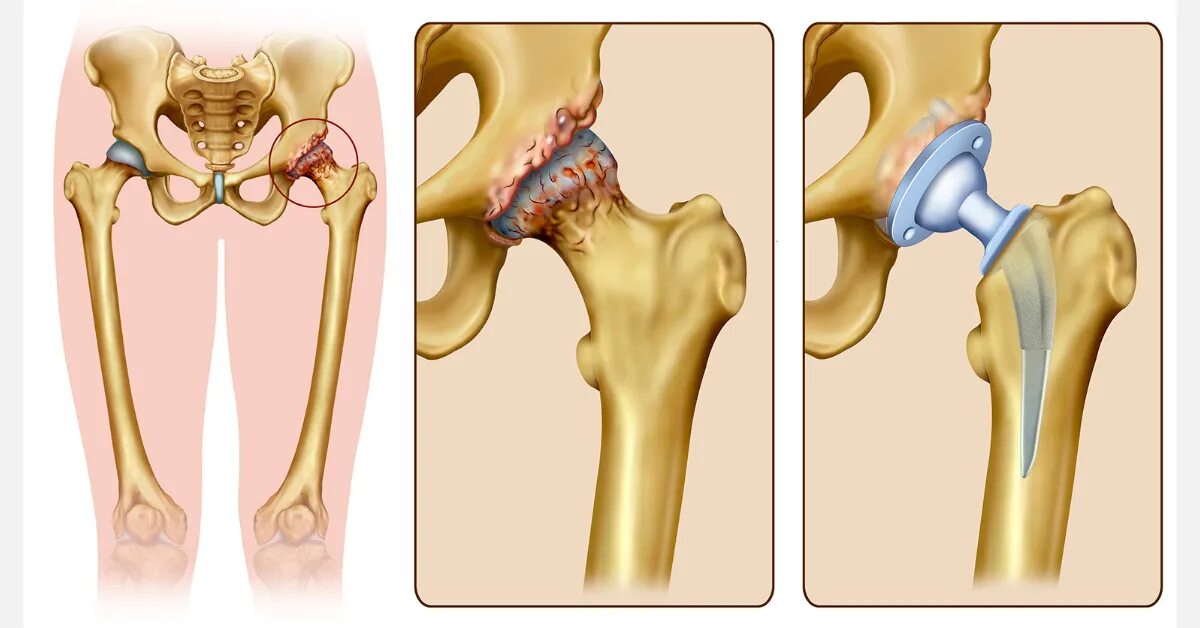

Коксартроз тазобедренного сустава код